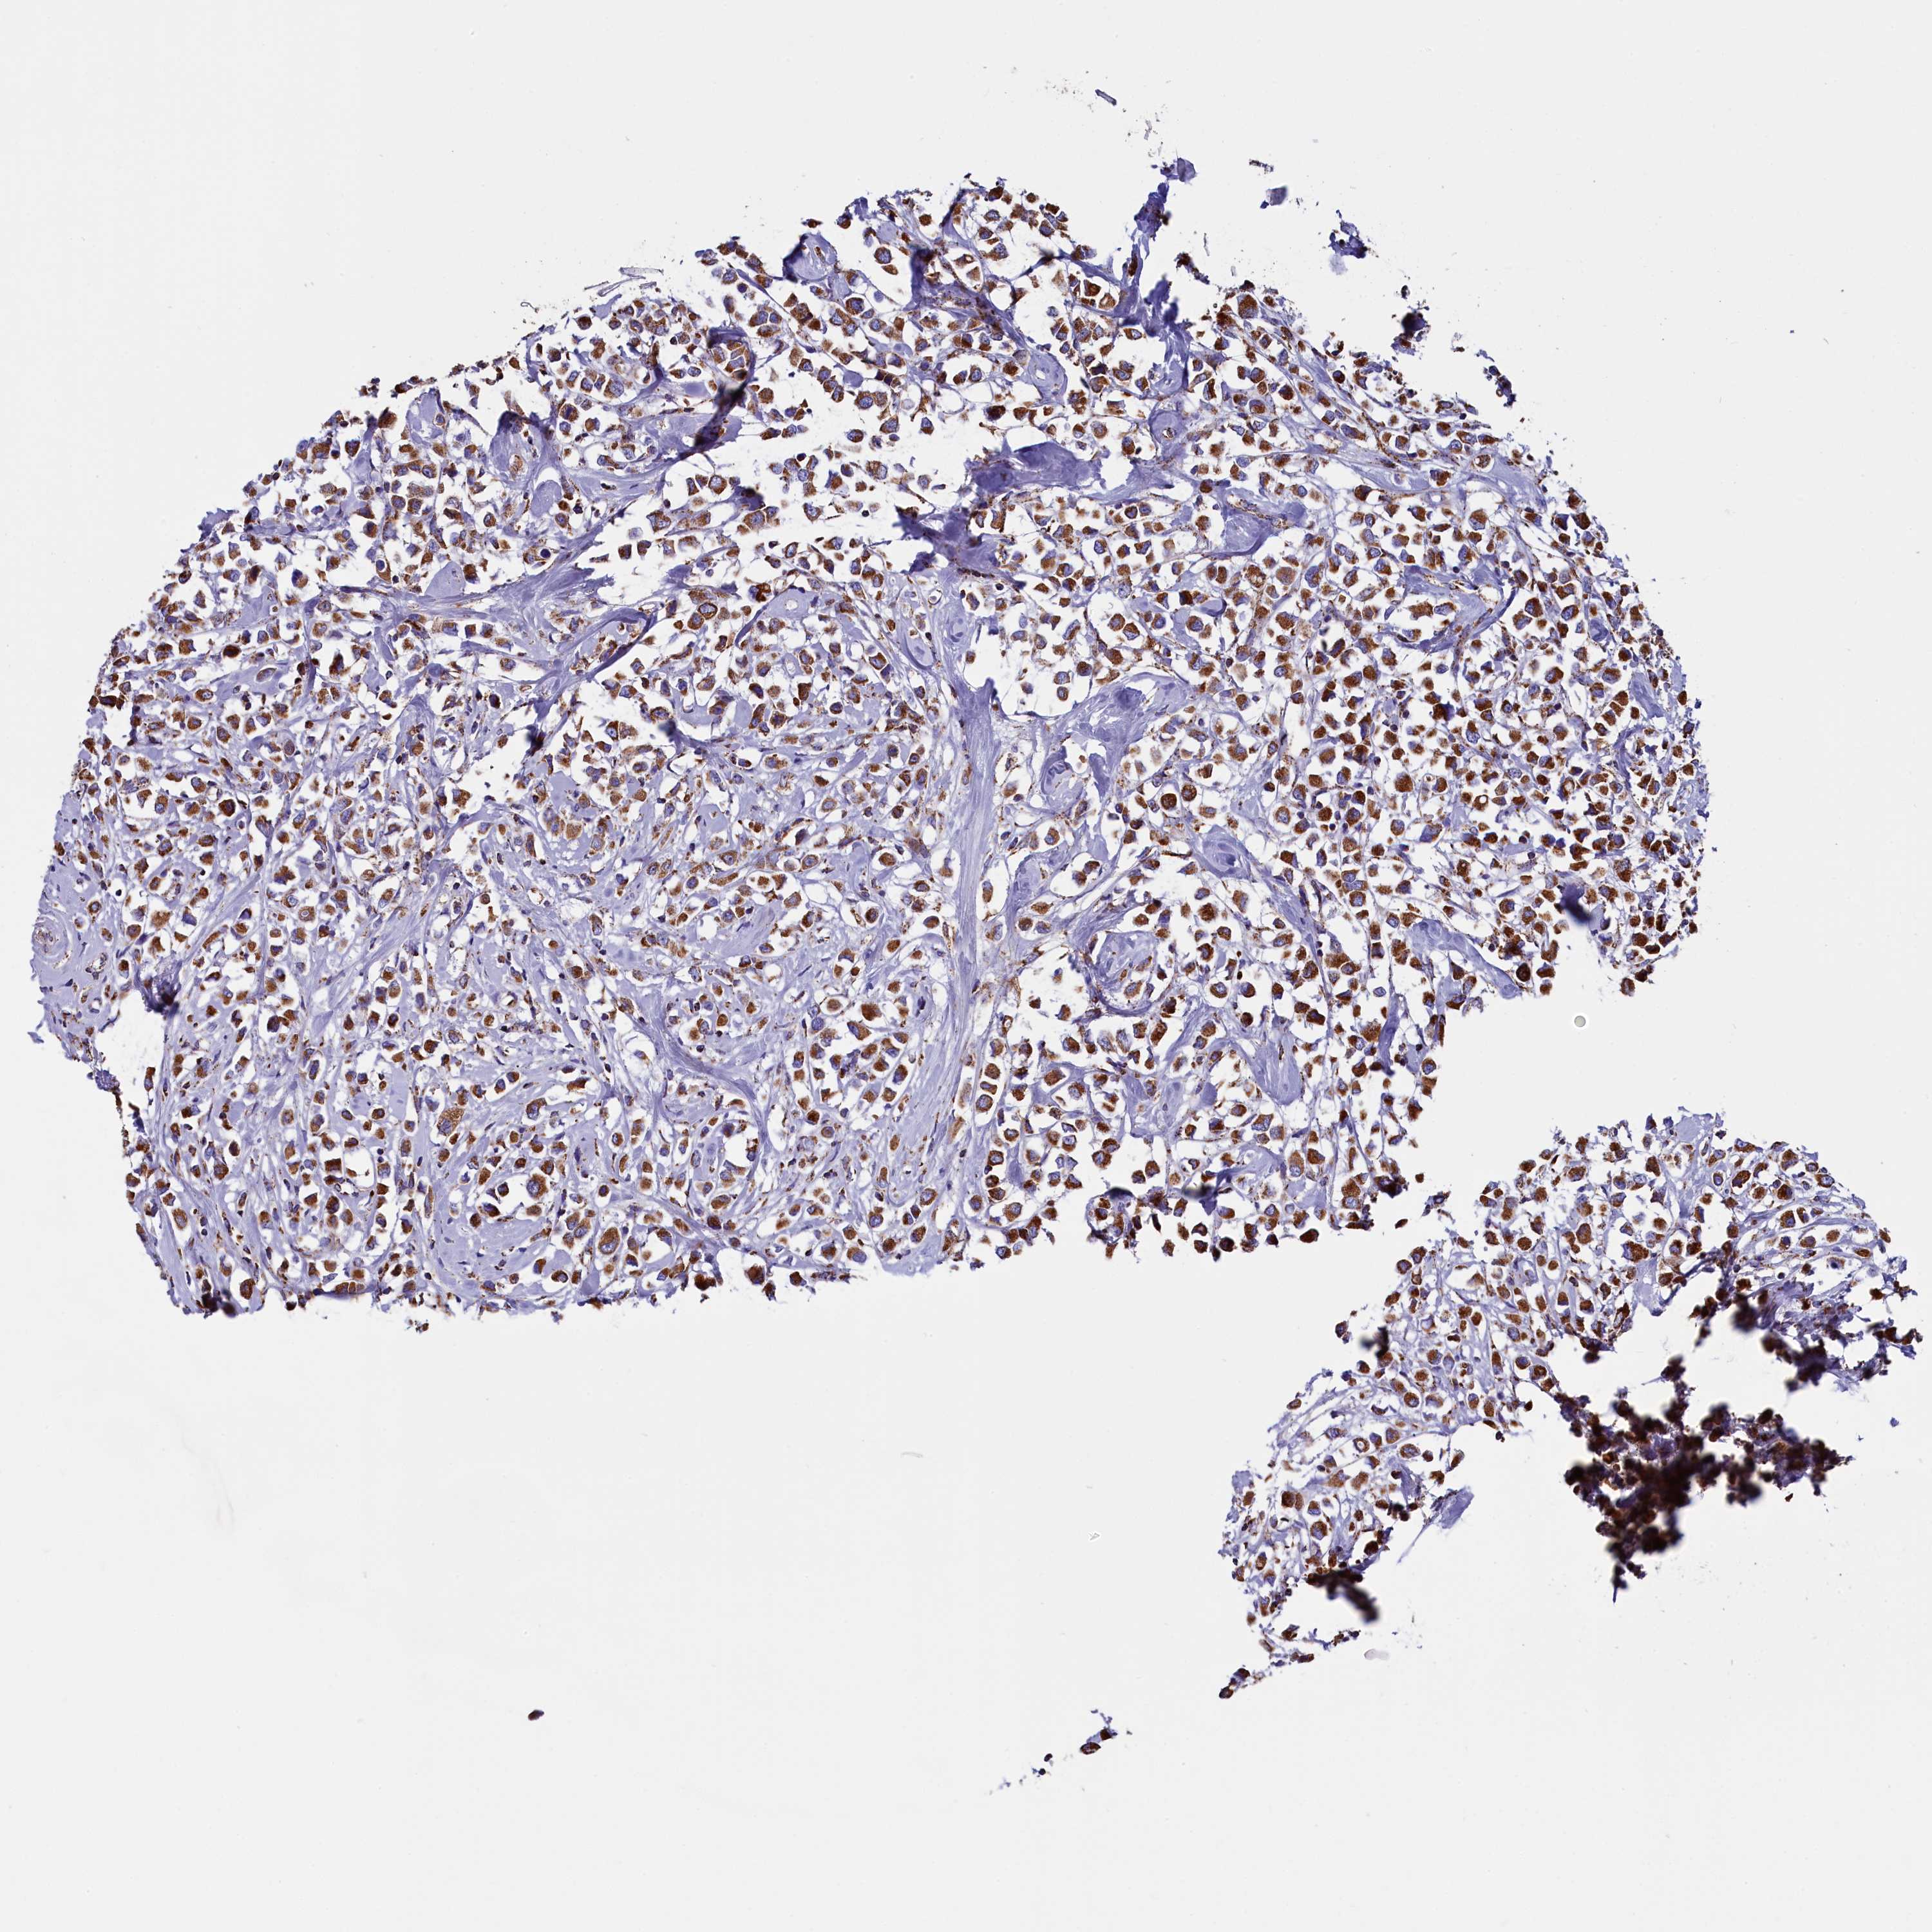

CANCER BREAST CANCER Show tissue menu

BRCA TCGA BRCA VALIDATION PROTEIN EXPRESSION